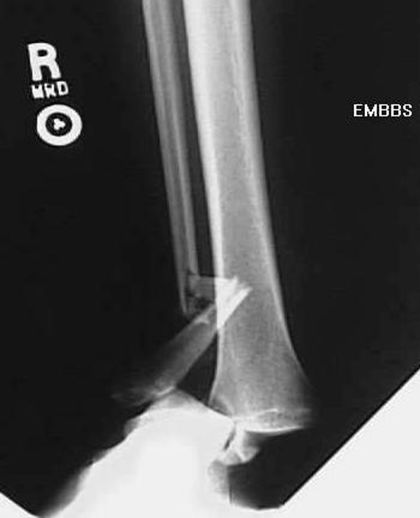

胫腓骨骨折

MaisonneuveFracture

• 腓骨中段骨折

• 下胫腓分离